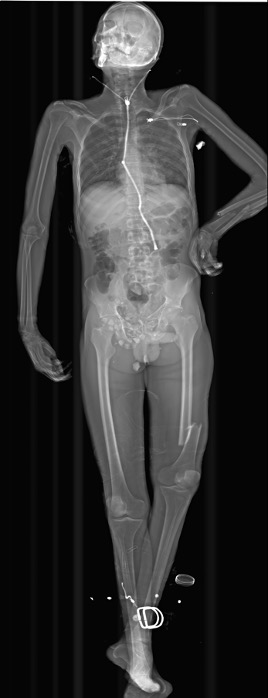

Klinik Görüntüler

Yukarıdaki örnek görüntüler, Lodox Xmplar-dr sisteminin her yaş ve vücut tipindeki hastalarda sunduğu yüksek çözünürlüklü tam vücut görüntüleme kapasitesini göstermektedir. Pediatrik hastalardan erişkinlere, düşük kilolu bireylerden yüksek vücut kitle indeksine sahip hastalara kadar geniş bir hasta grubunda net anatomik detay elde edilebilmektedir. Linear slot-scanning teknolojisi sayesinde kemik, yumuşak doku ve yabancı cisimler tek çekimde, ortalama 13–16 saniyede ve ultra düşük radyasyon dozu ile görüntülenir. Bu özellik, özellikle travma ve acil servis koşullarında hem hızlı tanı koymayı hem de radyasyona bağlı riskleri en aza indirmeyi mümkün kılar.